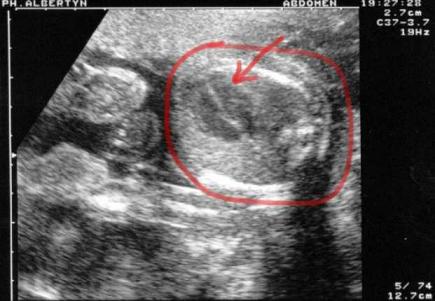

5th February

Marked with the read circle is a cross-section of Mariken's torso, and at the end of the arrow you can just make out her heart. It's beating at 140 bpm and in video you can clearly see the cadence of the 4 chambers which is a reassuring sight. As Katrien's awareness of Mariken grows and my ability to feel her move is still some weeks away, these ‘echo graph’ sessions are really my monthly date with my daughter. For now it's a father’s only way to experience the growth and increased movement of his child to be.